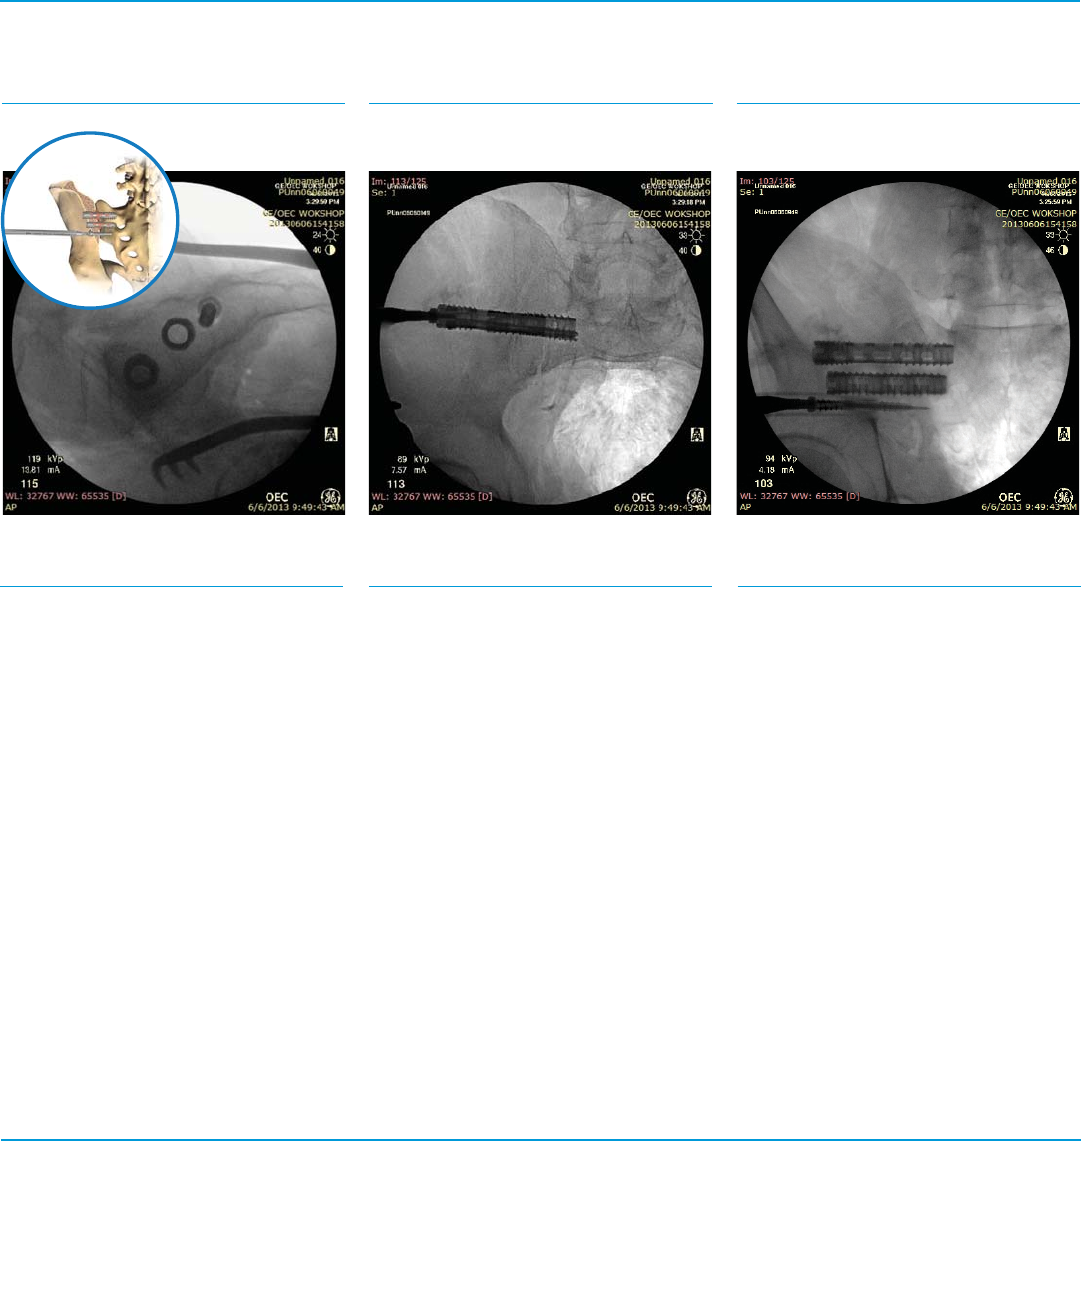

Fig. 16a SFig. 16b SFig. 16c S

Second Implant Insertion

Instruments

Step 16

Repeat Steps 4-14.

Lateral View (Fig. 16a)

Inlet View (Fig. 16b) Outlet View (Fig. 16c)